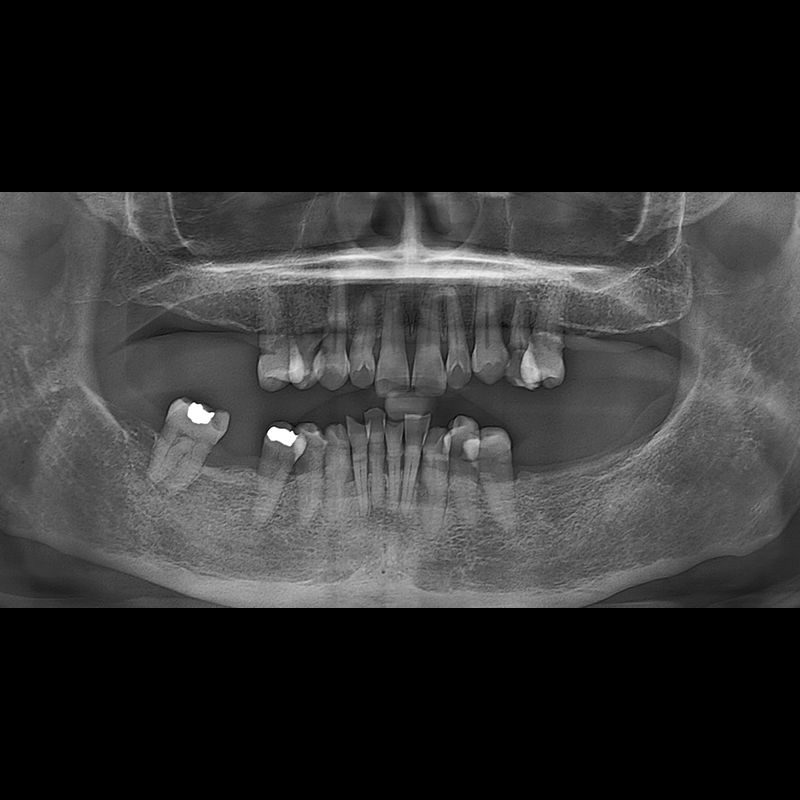

BEFORE AFTER

种植牙前后的照片 2025.05.30

在缺失的牙齿部分和难以挽救的牙齿位置植入了种植牙。